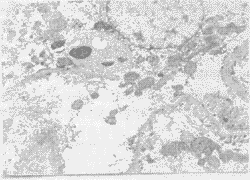

2.2 肾组织学变化 从大体标本上发现ANP组和ANP+NS组大鼠肾淤血水肿,伴有散在出血点和局灶性坏死。ANP组和ANP+NS组光镜下可见肾小球内有出血,间质充血和炎性细胞浸润。ANP组和ANP+NS组电镜下发现肾细胞内线粒体肿胀破裂,细胞膜损坏。生理盐水治疗无效,分别以生长抑素、生长激素治疗均有好转,联合治疗后可减轻组织损伤,接近正常水平(见图1,2)。

图1 ANP大鼠的肾组织电镜(×6000)肾细胞膜破裂,线粒体肿胀破裂,细胞器结构破坏。